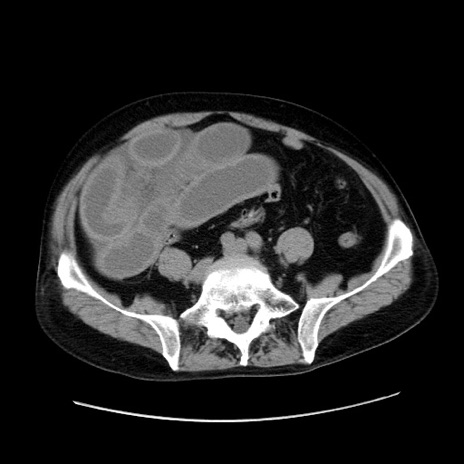

症例30(横断像)

【症例】80歳代男性

【主訴】臍周囲痛

【現病歴】約6時間前から臍下部痛が出現。次第に腹部膨隆・背部痛も生じてきたため来院。背部痛の場所は変化しない。

【既往歴】腎盂腎炎

【身体所見】意識清明、BT 36.3℃、BP  131/87mmHg、P 87bpm、SpO2 100%(RA)、臍周囲自発痛・圧痛あり、反跳痛なし、自発痛部位に一致して板状硬あり、腹部膨隆、腸雑音減弱、CVA tenderness両側陰性。

【データ】WBC 19600、CRP 0.33